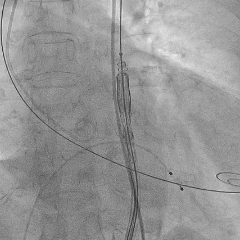

主动脉根部造影

瓣膜输送系统过弓,至主动脉根部